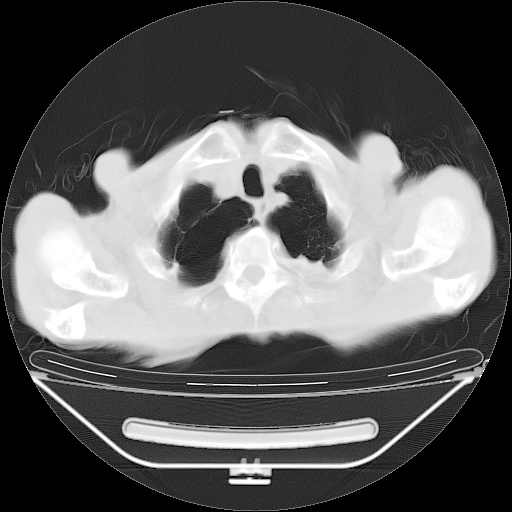

以下是引用zsl6918在2008-8-25 21:55:00的发言:[br]符合右肺周围性肺癌并肺内转移,左肺结核球。双肺肺气肿。腰椎附件转移。

以下是引用随光逐影在2008-8-25 22:03:00的发言:[br]1)考虑右肺下叶周围性肺癌并肺内转移,腰椎附件转移。2)左上肺结核(结核球形成)。3)双肺肺气肿(多发肺大泡形成)。4)双肺门区及纵隔内多发淋巴结钙化。